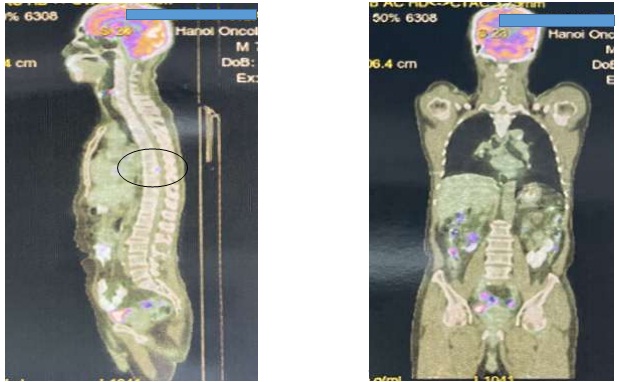

Hình ảnh PET/CT- FDG của bệnh nhân trước điều trị (1/2022): Hình ảnh tổn thương xương, tăng chuyển hóa FDG khu trú ở đốt sống D8 (SUVmax: 4,47). Không phát hiện hình ảnh tăng chuyển hóa FDG khu trú, bất thường ở nhu mô phổi hai bên và các vùng khác trong cơ thể (hình 1).

Hình 1: Ảnh chụp PET/CT trước điều trị